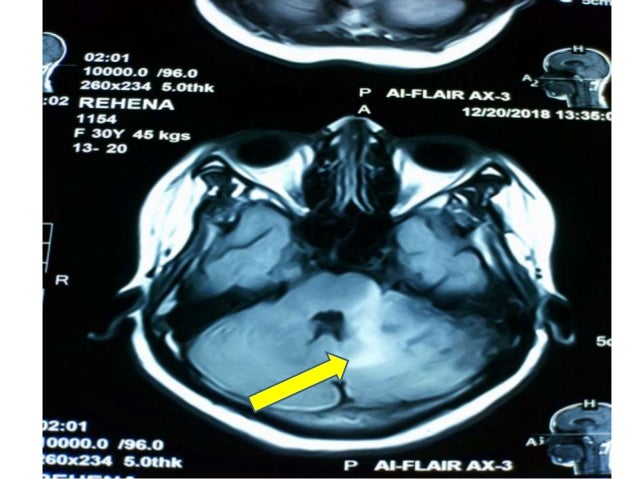

Cerebral Venous Sinus Thrombosis (CVST) Case Report

Residents and fellows contest rules | international ophthalmologists contest rules. Severe dehydration after competitive sport had induced cvst. Background and purpose—in cerebral venous thrombosis (cvt), the sensitivity of conventional mri sequences to detect clot in the sinuses or veins is incomplete and largely depends on the time elapsed since thrombus formation. H u h n a. The superior sagittal sinus and lateral sinuses were identified as the most commonly affected sinuses.

Cerebral venous sinus thrombosis occurs when a blood clot forms in the brain's venous sinuses.